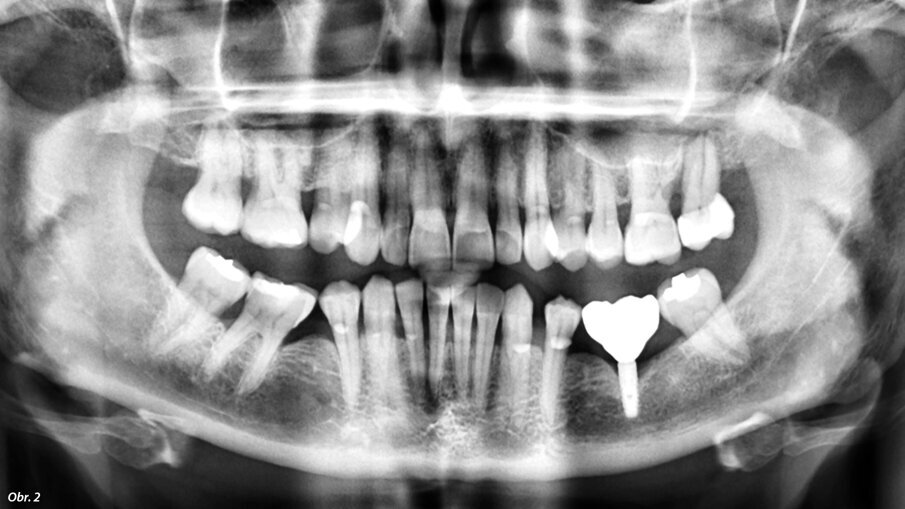

Na naše oddělení se dostavila pacientka, 52 let, s implantátem v místě 36, který byl zaveden na jiném pracovišti asi před 6 lety. Implantát vykazoval známky odhojení. Na OPG (ProMax, Planmeca) byl patrný velký úbytek kosti v okolí implantátu způsobený periimplantitidou (obr. 2). Proto byl implantát odstraněn, defekt byl exkochleován. Po 3 měsících bylo zhotovené CBCT (ProMax, Planmeca) pro plánování náhrady implantátu (obr. 3). Po zvážení všech možností (vertikální augmentace, short implant) jsme se rozhodli k zavedení tilted implantátu, který bude zaveden tak, aby míjel průběh mandibulárního kanálu (obr. 4). CBCT sken nám pomohl přesněji určit polohu mandibulárního kanálu. V programu jsem si následně vybral vhodný průměr i délku implantátu a určil jeho polohu tak, aby se vyhnul průběhu kanálu a zároveň respektoval aktuální nabídku kosti. Je velmi důležité podívat se na situaci z různých pohledů, abychom se ujistili, že jsme ošetření správně naplánovali.

Iniciační rentgenový snímek před začátkem ošetření.